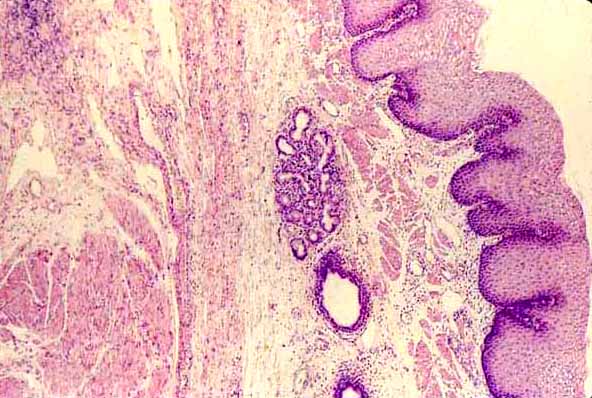

This is an amazing site due to the size and quality of the images. It was developed by the Histology and Virtual Microscopy Learning Resources Department at the University of Michigan Medical School. The SecondLook Series of Michigan eHistology is a mobile application for the iPad. It is a study aid that provides a series of histology slides for users to test their level of knowledge and their ability to recognize histological structures.

Este es un sitio increíble debido al tamaño y la calidad de las imágenes. Fue desarrollado por el Departamento de Histología y recursos de aprendizaje virtual de Microscopía de la Universidad de Michigan Medical School. La serie SecondLook de Michigan eHistology es una aplicación móvil para el IPAD. Es una ayuda al estudio que ofrece una serie de cortes histológicos de los usuarios probar su nivel de conocimientos y su capacidad para reconocer las estructuras histológicas.